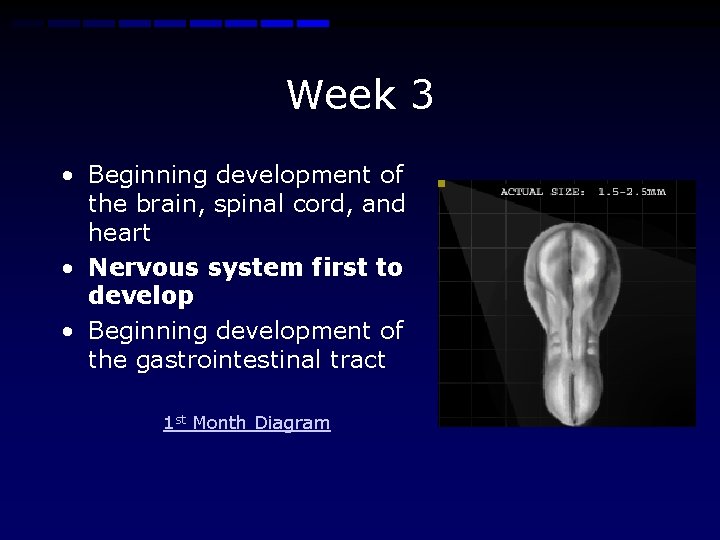

Week 3 • Beginning development of the brain, spinal cord, and heart • Nervous system first to develop • Beginning development of the gastrointestinal tract 1 st Month Diagram